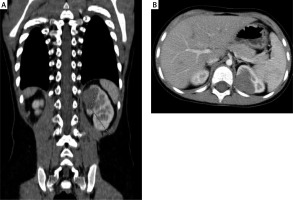

The mean tumor volume before and after chemotherapy was 174.4 ml (range: 14.7–501 ml) and 32.8 ml (range: 4.3–68 ml) respectively. Seven nephrectomies and one left heminephrectomy (NSS) (tumor volume 14.7 ml before chemotherapy (Photos 1 A, B) and 4.3 ml after chemotherapy (Photos 2 A, B)) were performed. LN was performed via the transperitoneal approach in all cases. No patients had an intraoperative tumor rupture. Median operative time for LN was 120 min (range: 100–195 min). The operative time for laparoscopic NSS was 210 min. No conversions to open surgery were needed. The specimen was extracted in a bag without morcellation in all cases. The umbilical trocar was removed. An endobag was inserted through the incision. The specimen was placed into it, and the abdominal cavity was deflated. For the extraction, the umbilical incision was extended 1–2 cm up and down according to the size of the specimen. All children had an attempt of lymph node sampling. Their number per pathology assessment ranged from 0 to 5 (median 2). In only one patient the number of harvested lymph nodes was zero. In this case no lymph nodes were observed visually and adipose tissue in the station which should contain small lymph nodes was removed. In the remaining patients the number of sampled lymph nodes was 2 in 5 cases, 3 in 1 case and 5 also in 1 case. All analyzed lymph nodes were negative for malignancy. The mean time of hospitalization was 3.5 days (range: 2–17).

There were no intraoperative events. One complication after heminephrectomy occurred. A 5-year-old girl (patient no. 1) with a peripheral tumor of the left kidney was qualified for nephron-sparing surgery after a multidisciplinary tumor board meeting. NSS seemed possible because of the polar location and the small size of the tumor. The tumor size was 37 × 23 × 33 mm before and 18 × 20 × 23 mm after chemotherapy. An EinsteinVision 2.0 3D Camera System was used. The patient was placed in the decubitus position and 4 ports were placed (umbilicus – 12 mm, scope; middle epigastrium – 5 mm; left midabdomen – 5 mm; middle hypogastrium – 10 mm). A vessel loop was placed to secure control of the main renal artery and vein. The renal vein and artery to the upper pole of the kidney were controlled using Hem-O-Lock clips. The boundaries of the tumor were marked on the renal capsule under intraoperative US guidance. The upper pole of the kidney was resected using scissors (without arterial clamping – “zero-ischemia” resection). An extra rim of renal parenchyma was removed circumferentially to improve the radicality of the resection. The renal calyx and parenchyma were sutured using Vicryl 3-0 continuous suture and secured with TachoSil. The urinary leakage was observed postoperatively. Drainage of fluid (biochemically confirmed urine) was about 200 ml/day. Six days after laparoscopic NSS a cystoscopy with ureteral catheterization was done and urinary leakage was confirmed. The child required an open reoperation 8 days after LN. Partial ureteropelvic junction disruption (iatrogenic event during the first cystoscopy?) and leakage from the renal calyx were found. Ureteropelvic junction obstruction was diagnosed, although there was no renal pelvis dilatation on the initial imaging. The pyeloplasty was performed with double J stent placement to protect the anastomosis. An opened calyx was sutured using interrupted Vicryl 4-0 sutures. The further postoperative course was uneventful. The urinary leakage had resolved and the double J stent was removed after 2 months.